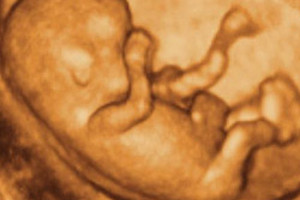

fot. Internet USG obrazuje narządy wewnętrzne za pomocą odbicia wiązki ultradźwięków przetwarzanych następnie na ekran komputera. Umożliwia to precyzyjna...